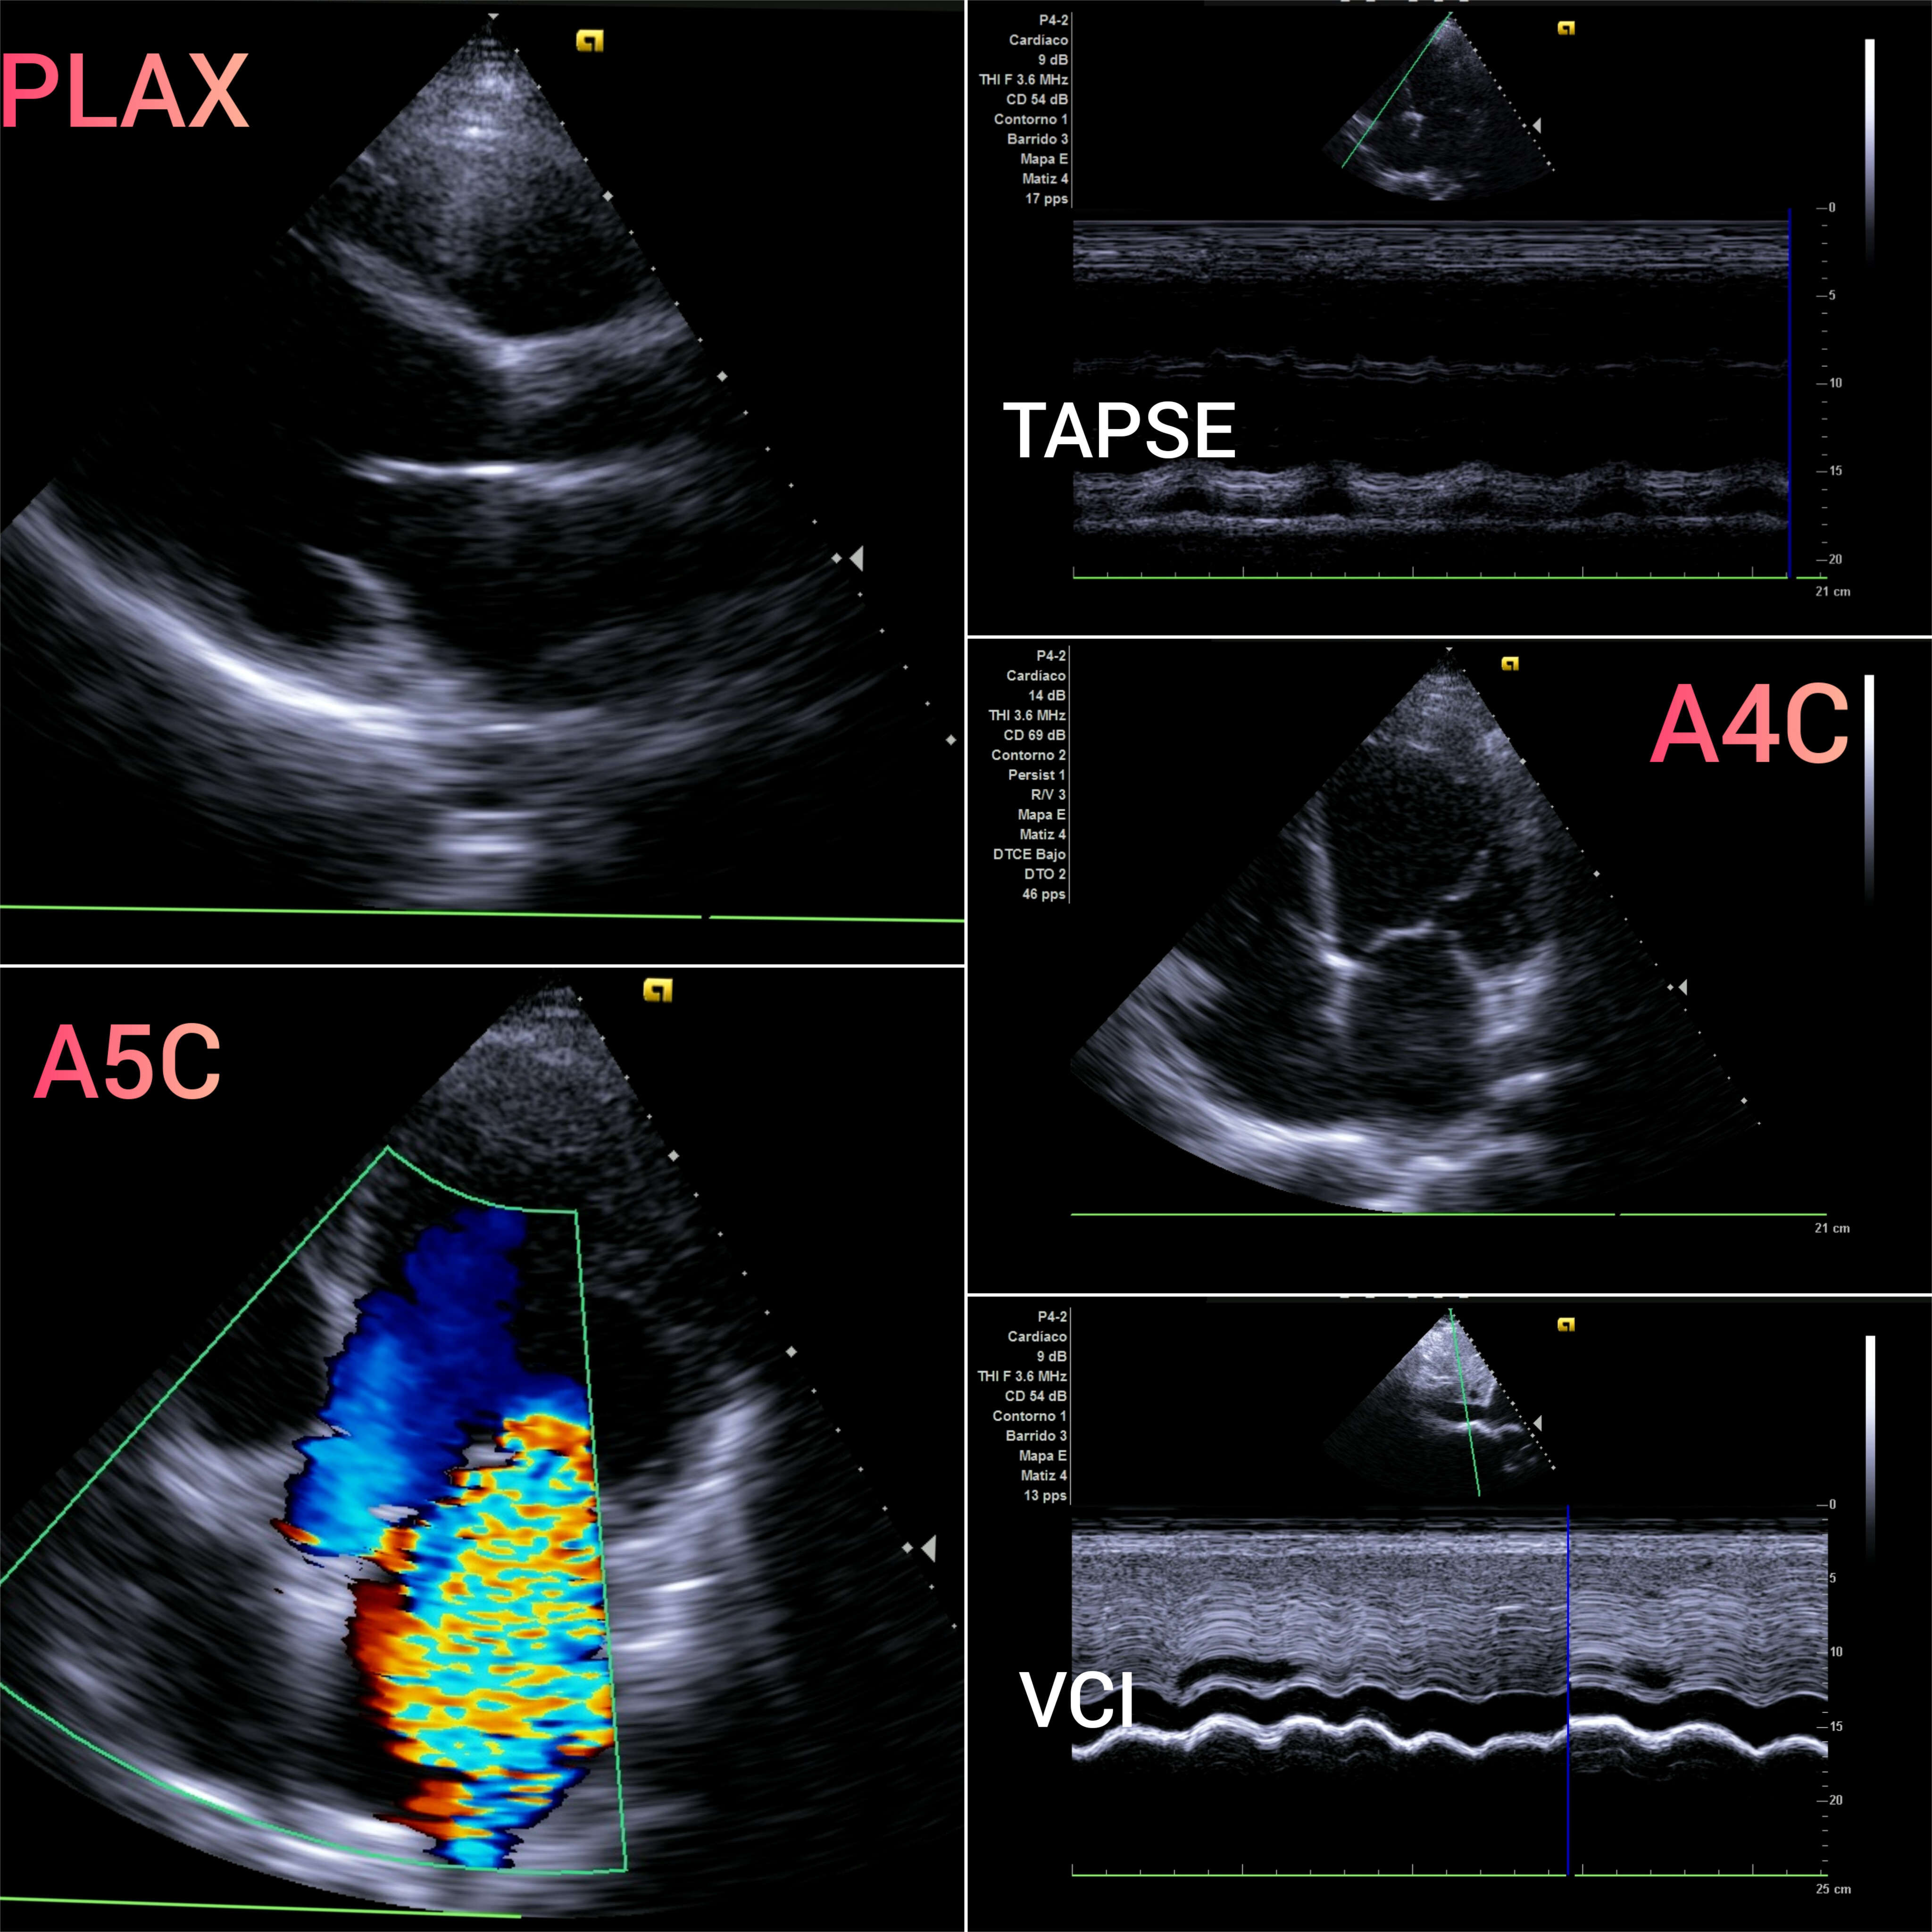

VEXUS: Vena cava inferior VCI 2,1 con colapsabilidad > 50%; Flujo portal y renal continuo.

EcoCardioscopia: Mejoría de contractilidad subjetivamente respecto a previo, cavidades izquierdas dilatatadas tanto VI como AI.

Desde la última descompensación por IC el paciente mantiene aceptable tolerancia al ejercicio, cumplimiento terapéutico no así en tóxicos, congruente con los hallazgos de ecocardioscopia. Ante antecedentes familiares de cardiopatía, alteración genética y deseo de descendencia, remitimos de nuevo a Genética. Ademas, recomendamos estudio genético de la madre y la hermana.